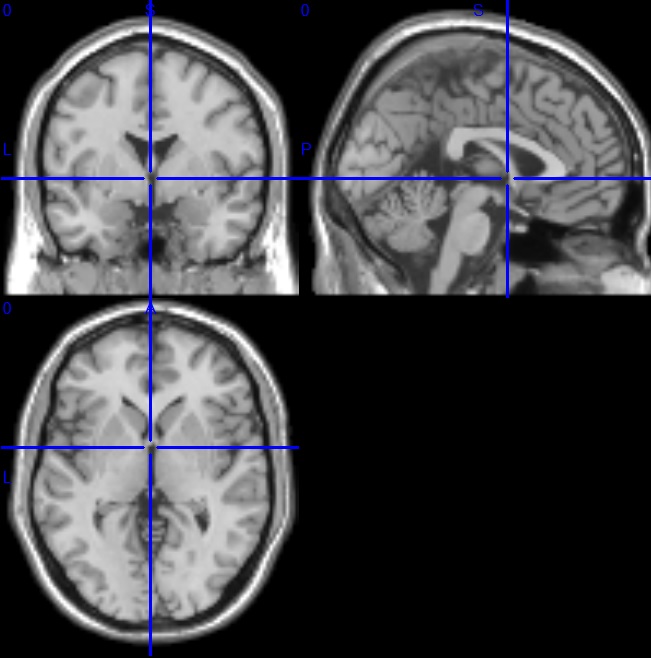

fMRI解析マニュアル

fMRIデータの前処理